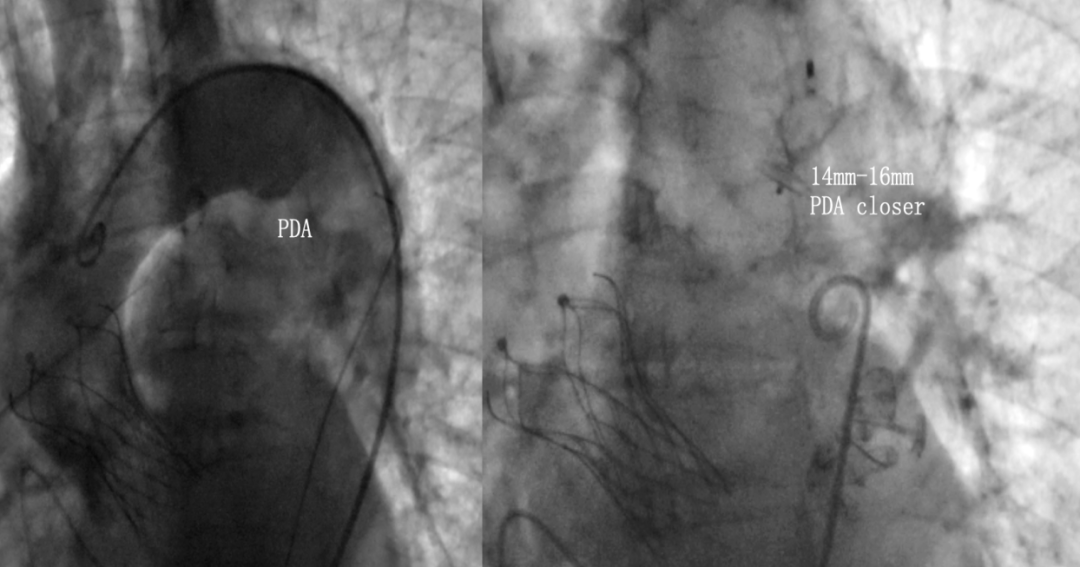

术前发现患者合并动脉导管未闭

管型6.2mmx12.9mm

6. 患者合并动脉导管未闭,计划主动脉瓣植入完成后经主动脉路径完成动脉导管未闭封堵。

经主动脉路径植入14mm-16mm PDA封堵器